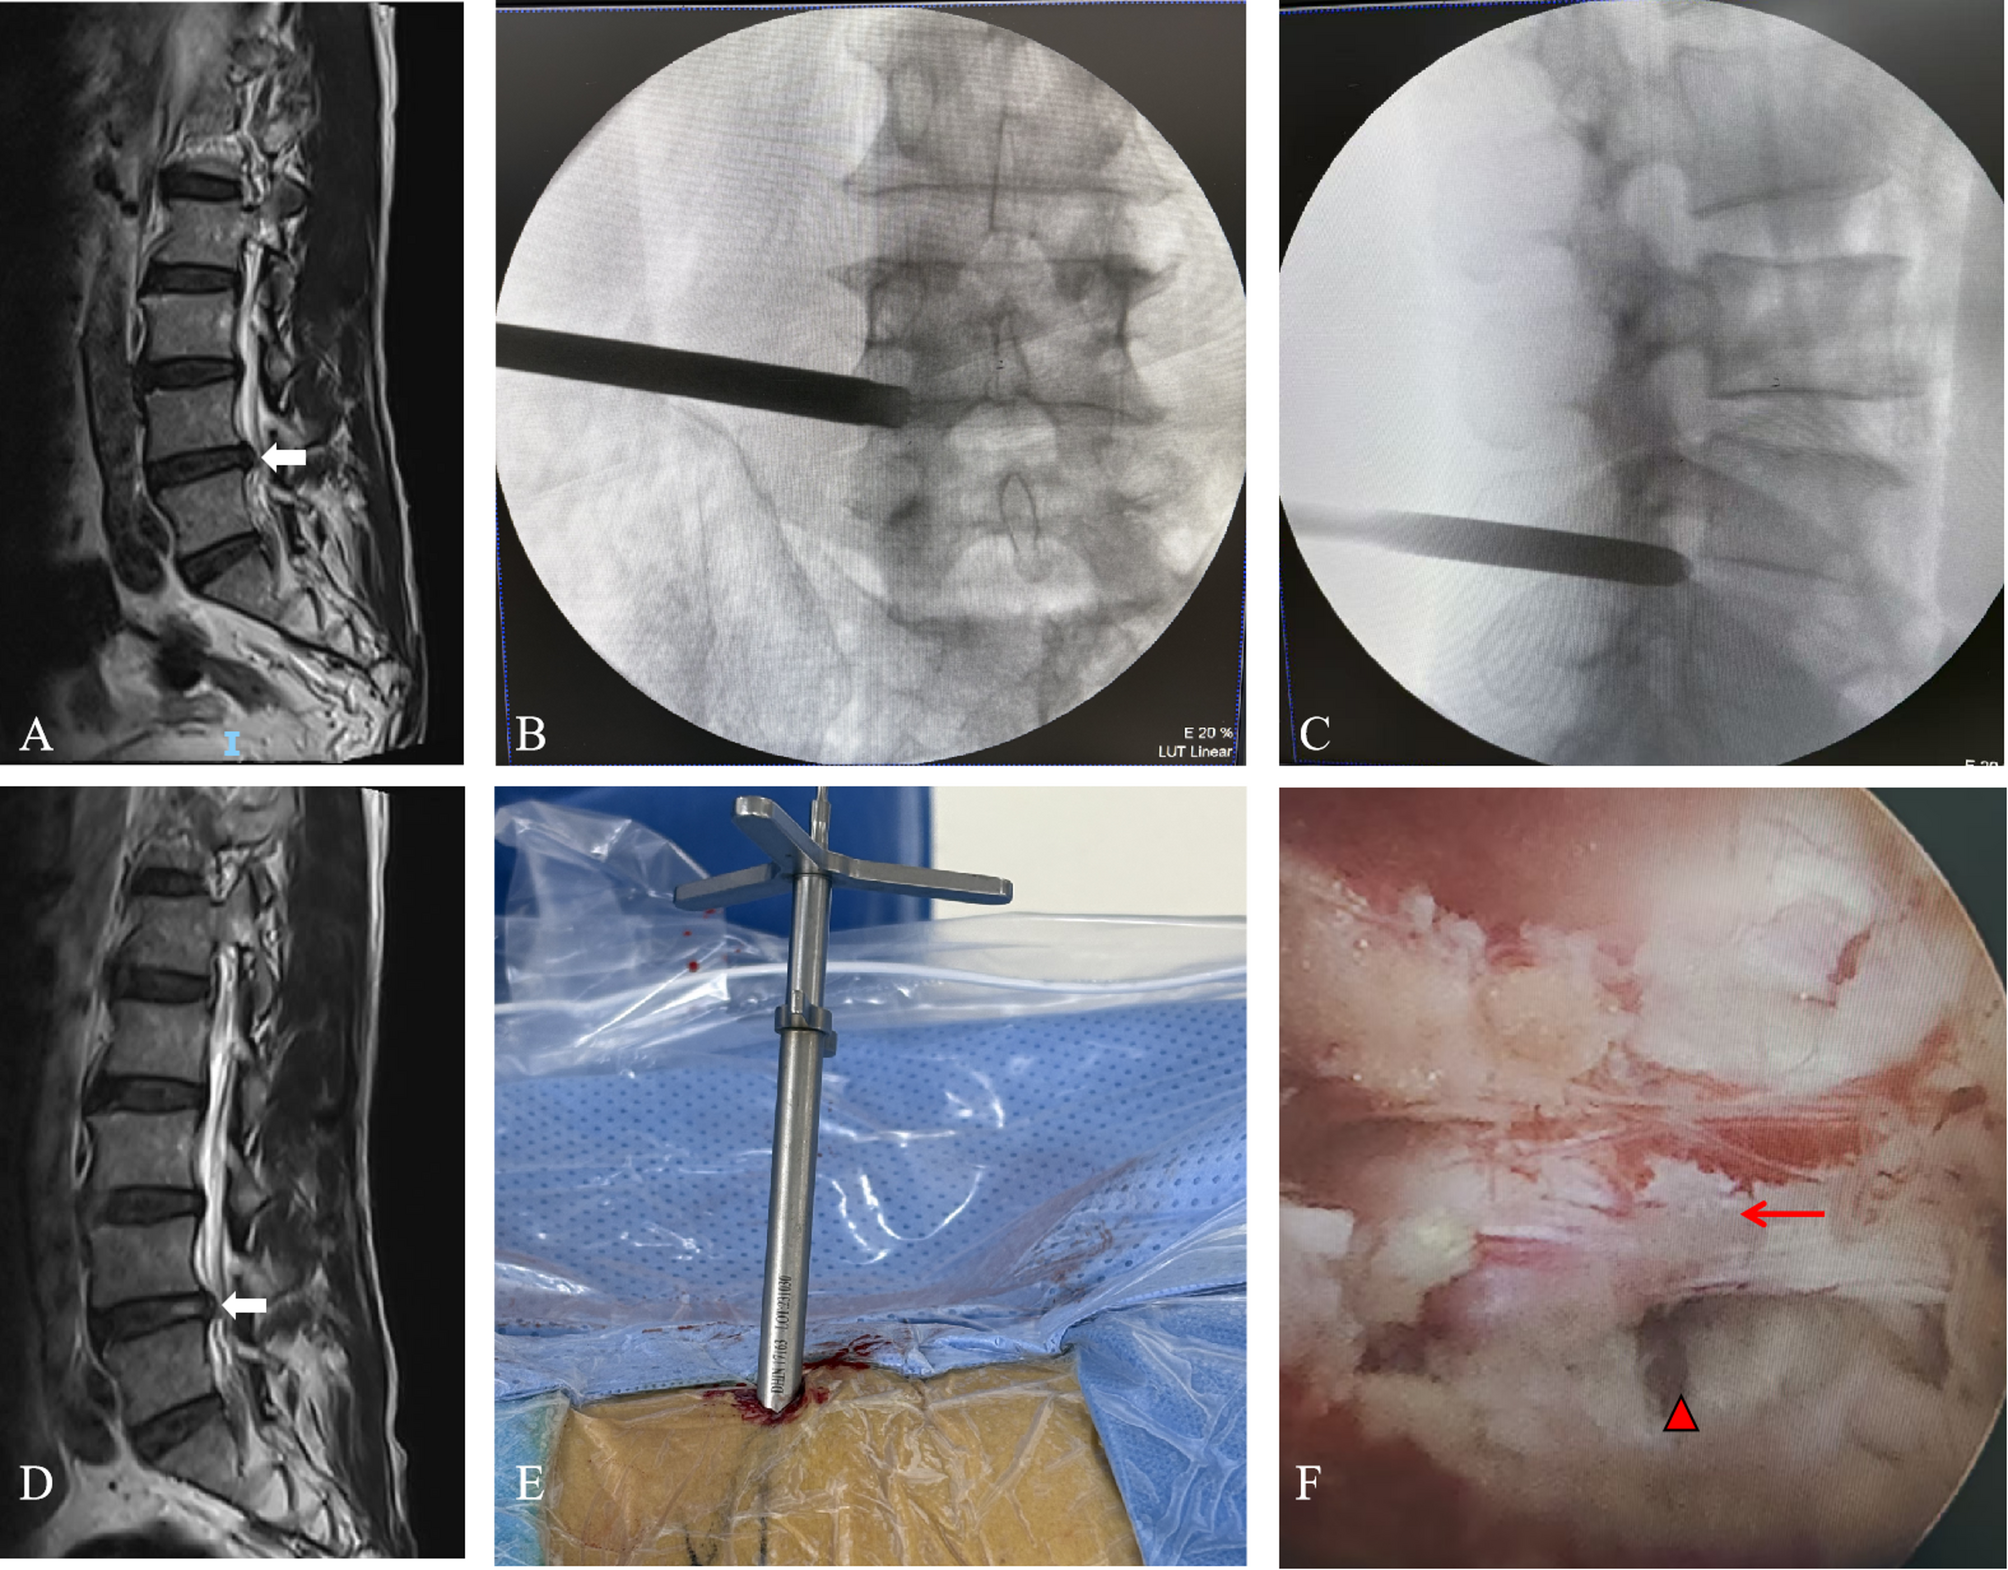

Fig. 1

Percutaneous endoscopic transforaminal discectomy (PETD) was performed on an 88-year-old male patient with L4-L5 disc herniation. (A) Preoperative magnetic resonance image indicating L4-L5 disc herniation (arrow). (B) Intraoperative anteroposterior radiograph demonstrating the position of the working cannula. (C) Intraoperative lateral radiograph confirming the placement of the working cannula at the posterosuperior margin of the vertebral body. (D) Postoperative magnetic resonance image revealing a substantial reduction of the L4-L5 disc herniation (arrow). (E) Operative working cannula placed. (F) Intraoperative endoscopic view illustrating the nerve root (arrow)and intervertebral space (triangle).